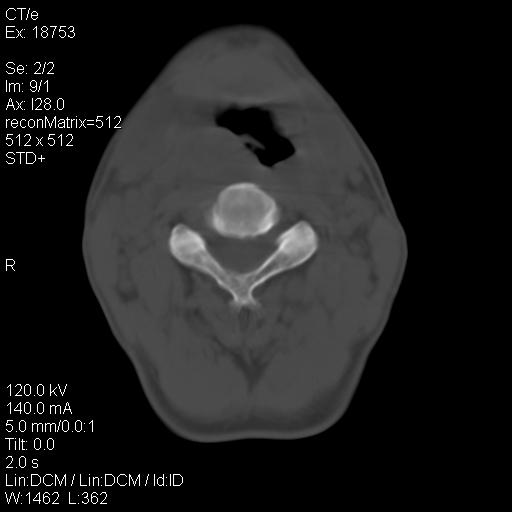

标题: CT21693:男 58岁 右侧咽部疼她2天余 PE:右侧扁桃体肿大 压痛 [打印本页]

标题: CT21693:男 58岁 右侧咽部疼她2天余 PE:右侧扁桃体肿大 压痛

1 弥漫性肿胀,与周围组织分界清晰,发病急,有明显症状,考虑急性炎症【wbc]

弥漫性肿胀,与周围组织分界不清,发病急,有明显症状,考虑:感染性病变!

右化脓性扁桃体炎症伴咽后壁脓肿形成.